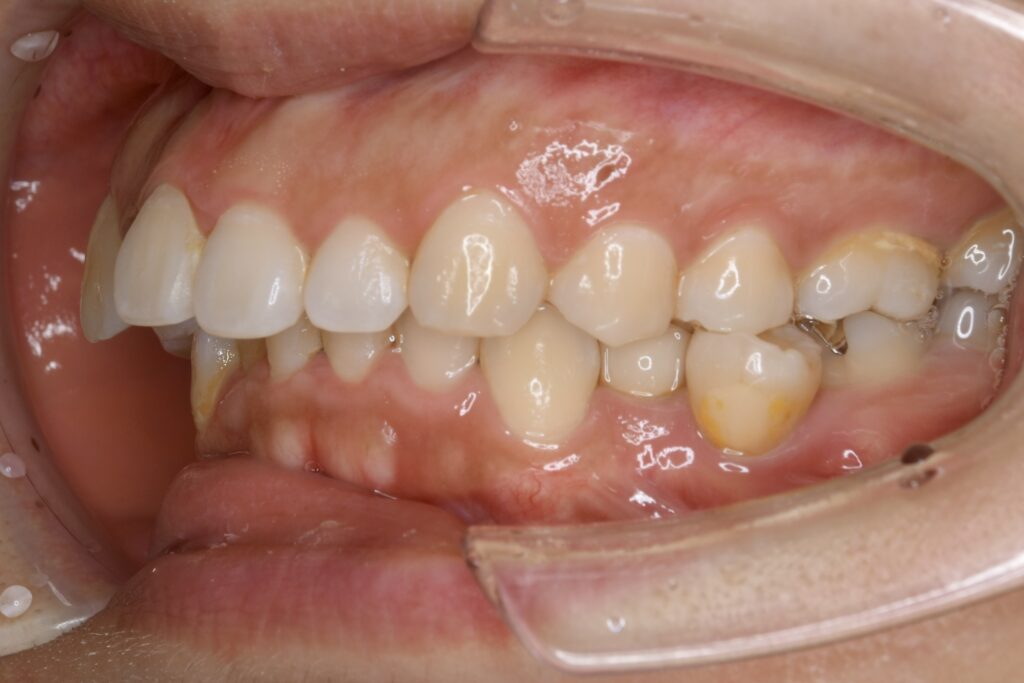

32歳 女性 治療期間:1年7ヶ月

BEFORE

診断名・主な症状 叢生を伴う上顎前突

治療内容 上下とも歯を2本抜いて、上の前歯を後方に引きながら、でこぼこを治しました。